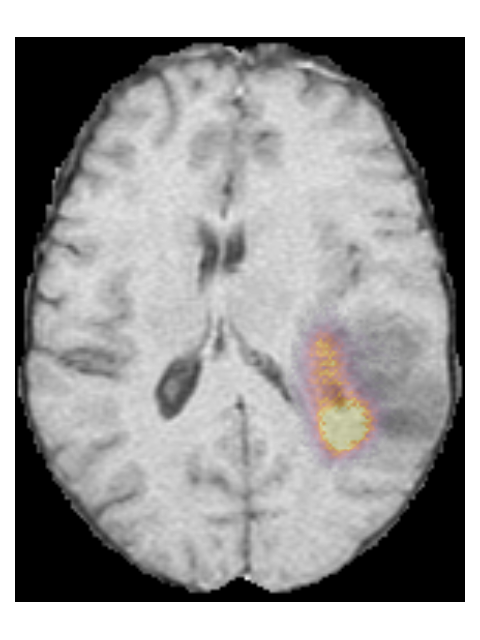

To provide insight into the behavior of our model we created saliency maps, which show which parts of the scans contributed the most to the prediction. These saliency maps are shown in Figure 6 for two example patients from the test set. It can be seen that for the LGG the network focused on a bright rim in the T2w-FLAIR scan, whereas for the HGG it focused on the enhancement in the post-contrast T1w scan. To aid further interpretation, we provide visualizations of selected filter outputs in the network in Appendix D, which also show that the network focuses on the tumor, and these filters seem to recognize specific imaging features such as the contrast enhancement and T2w-FLAIR brightness.